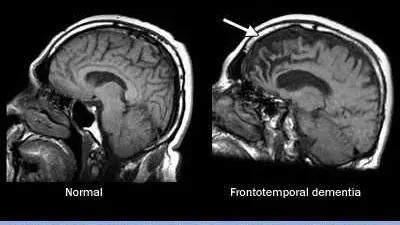

Demenza frontotemporale, che cos’è e quali sono i sntomi

Un gruppo non comune di disturbi può causare cambiamenti nella personalità, nel comportamento, nel linguaggio, nel movimento.leggi